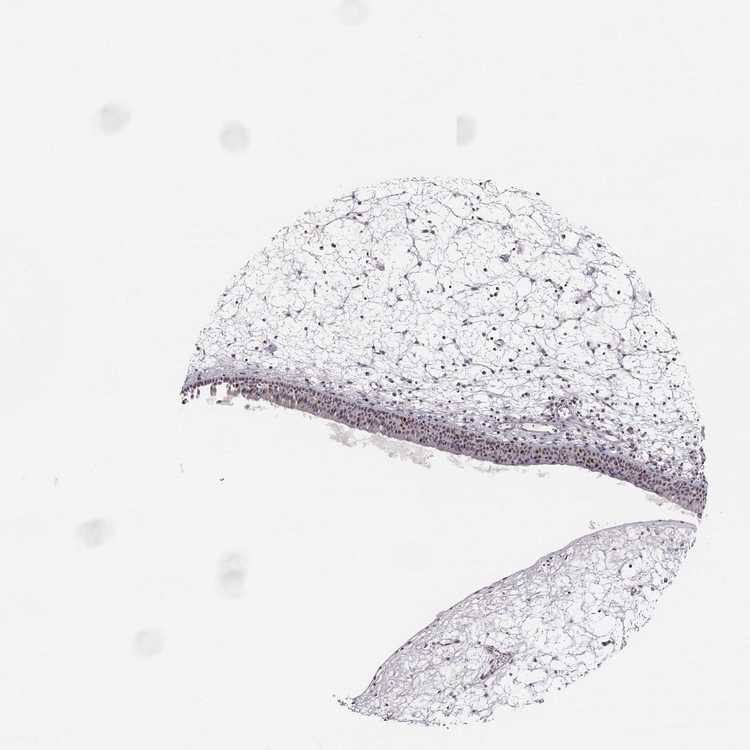

TISSUE PRIMARY DATA NASOPHARYNX Show tissue menu

NASOPHARYNX - Antibody stainingi

Antibody staining in the annotated cell types in the current human tissue is reported as not detected, low, medium, or high, based on conventional immunohistochemistry profiling in selected tissues. This score is based on the combination of the staining intensity and fraction of stained cells.

Each image is clickable and will lead to virtual microscopy that enables deeper exploration of all samples and also displays staining intensity scores, fraction scores and subcellular localization as well as patient and tissue information for each sample.

Antibody CAB016117

Basal cells Not detected

Ciliated cells (cell body) Medium

Ciliated cells (cilia axoneme) Not detected

Ciliated cells (ciliary rootlets) Not detected

Ciliated cells (tip of cilia) Not detected

Goblet cells Not detected